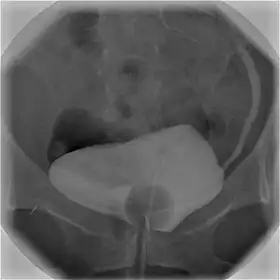

![]() Cystography image showing contrast in the urinary bladder and left ureter (right side of image). | |